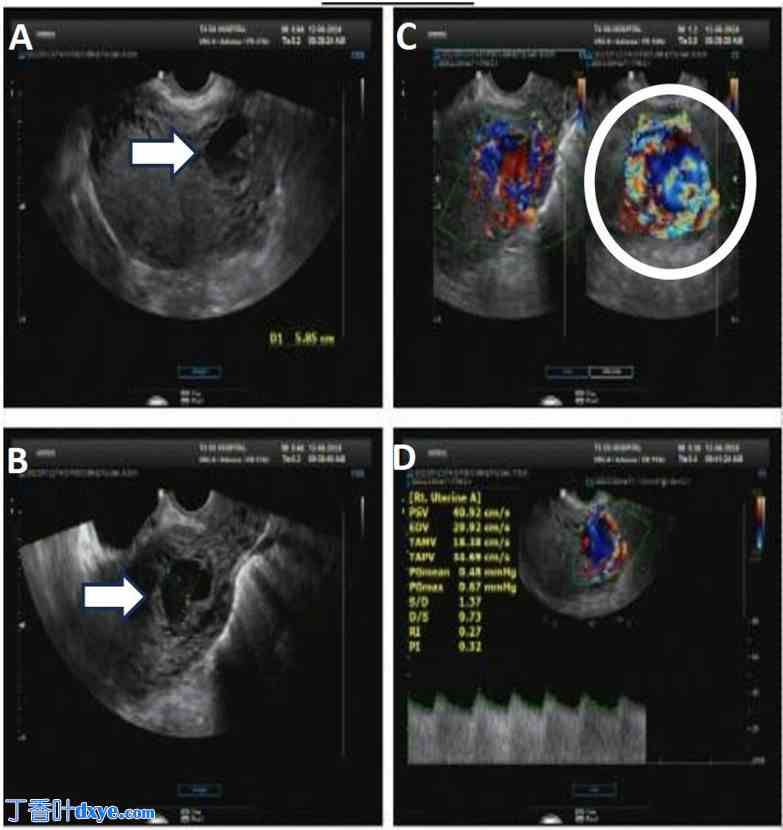

一名31岁的越南女性患者,孕2产1,因疑似妊娠入院。患者曾行一次剖宫产,无社会心理史。患者否认饮酒、吸烟或吸食大麻。家族史无异常。患者生命体征稳定。患者主诉月经推迟,轻微阴道出血,无腹痛。妇科检查显示,子宫大小与孕7周相符。窥器检查显示宫颈完全正常。β-人绒毛膜促性腺激素 (β-hCG) 水平为58,644 mUI/mL,确诊妊娠。超声扫描发现宫腔空虚,妊娠囊不规则,无胚胎,位于上次剖宫产疤痕部位附近约20毫米处。然而,由于多普勒超声检查可见血管增生,CSEP诊断与部分性葡萄胎(图1A、B)需仔细鉴别。患者在手术室超声引导下接受了宫腔穿刺术。术后,70克妊娠产物送检进行组织病理学检查(图2A、B)。总出血量为20毫升。24小时后,患者的β-hCG水平降至32,240 mUI/mL。

图1.

经阴道超声检查子宫矢状面显示,先前剖宫产部位存在多个低回声区域,并延伸至宫底(A)。经阴道彩色多普勒超声检查,诊断为剖宫产瘢痕异位妊娠,但由于存在血管丰富的肿块(B),无法排除部分性葡萄胎的可能。